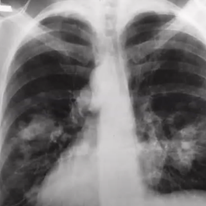

לא רק עישון: הרגלי התזונה שמעלים דרמטית את הסיכון לסרטן ריאותמחקר מצא קשר חזק בין צריכת שומן רווי לסיכון לחלות בסרטן הקטלני בעולם. מחקר נוסף מצא כי גמילה מעישון בכל שלב, גם לאחר אבחון בסרטן הריאה מעלה משמעותית את סיכויי ההישרדותישראל שמאיישראל שמאי